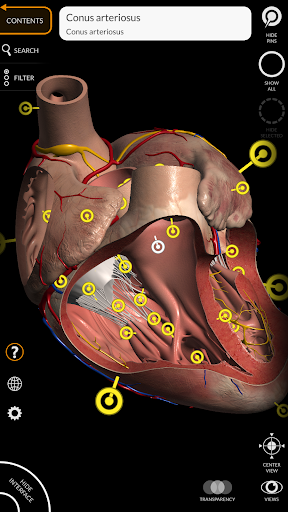

"Anatomy 3D Atlas" дозволяє легко та інтерактивно вивчати анатомію людини.

Завдяки простому та інтуїтивно зрозумілому інтерфейсу можна спостерігати кожну анатомічну структуру під будь-яким кутом.

Анатомічні 3D-моделі особливо деталізовані та мають текстури з роздільною здатністю до 4k.

• Серцево-судинна система

• Вибравши модель або шпильку, з’явиться відповідний анатомічний термін

• Серцево-судинна система